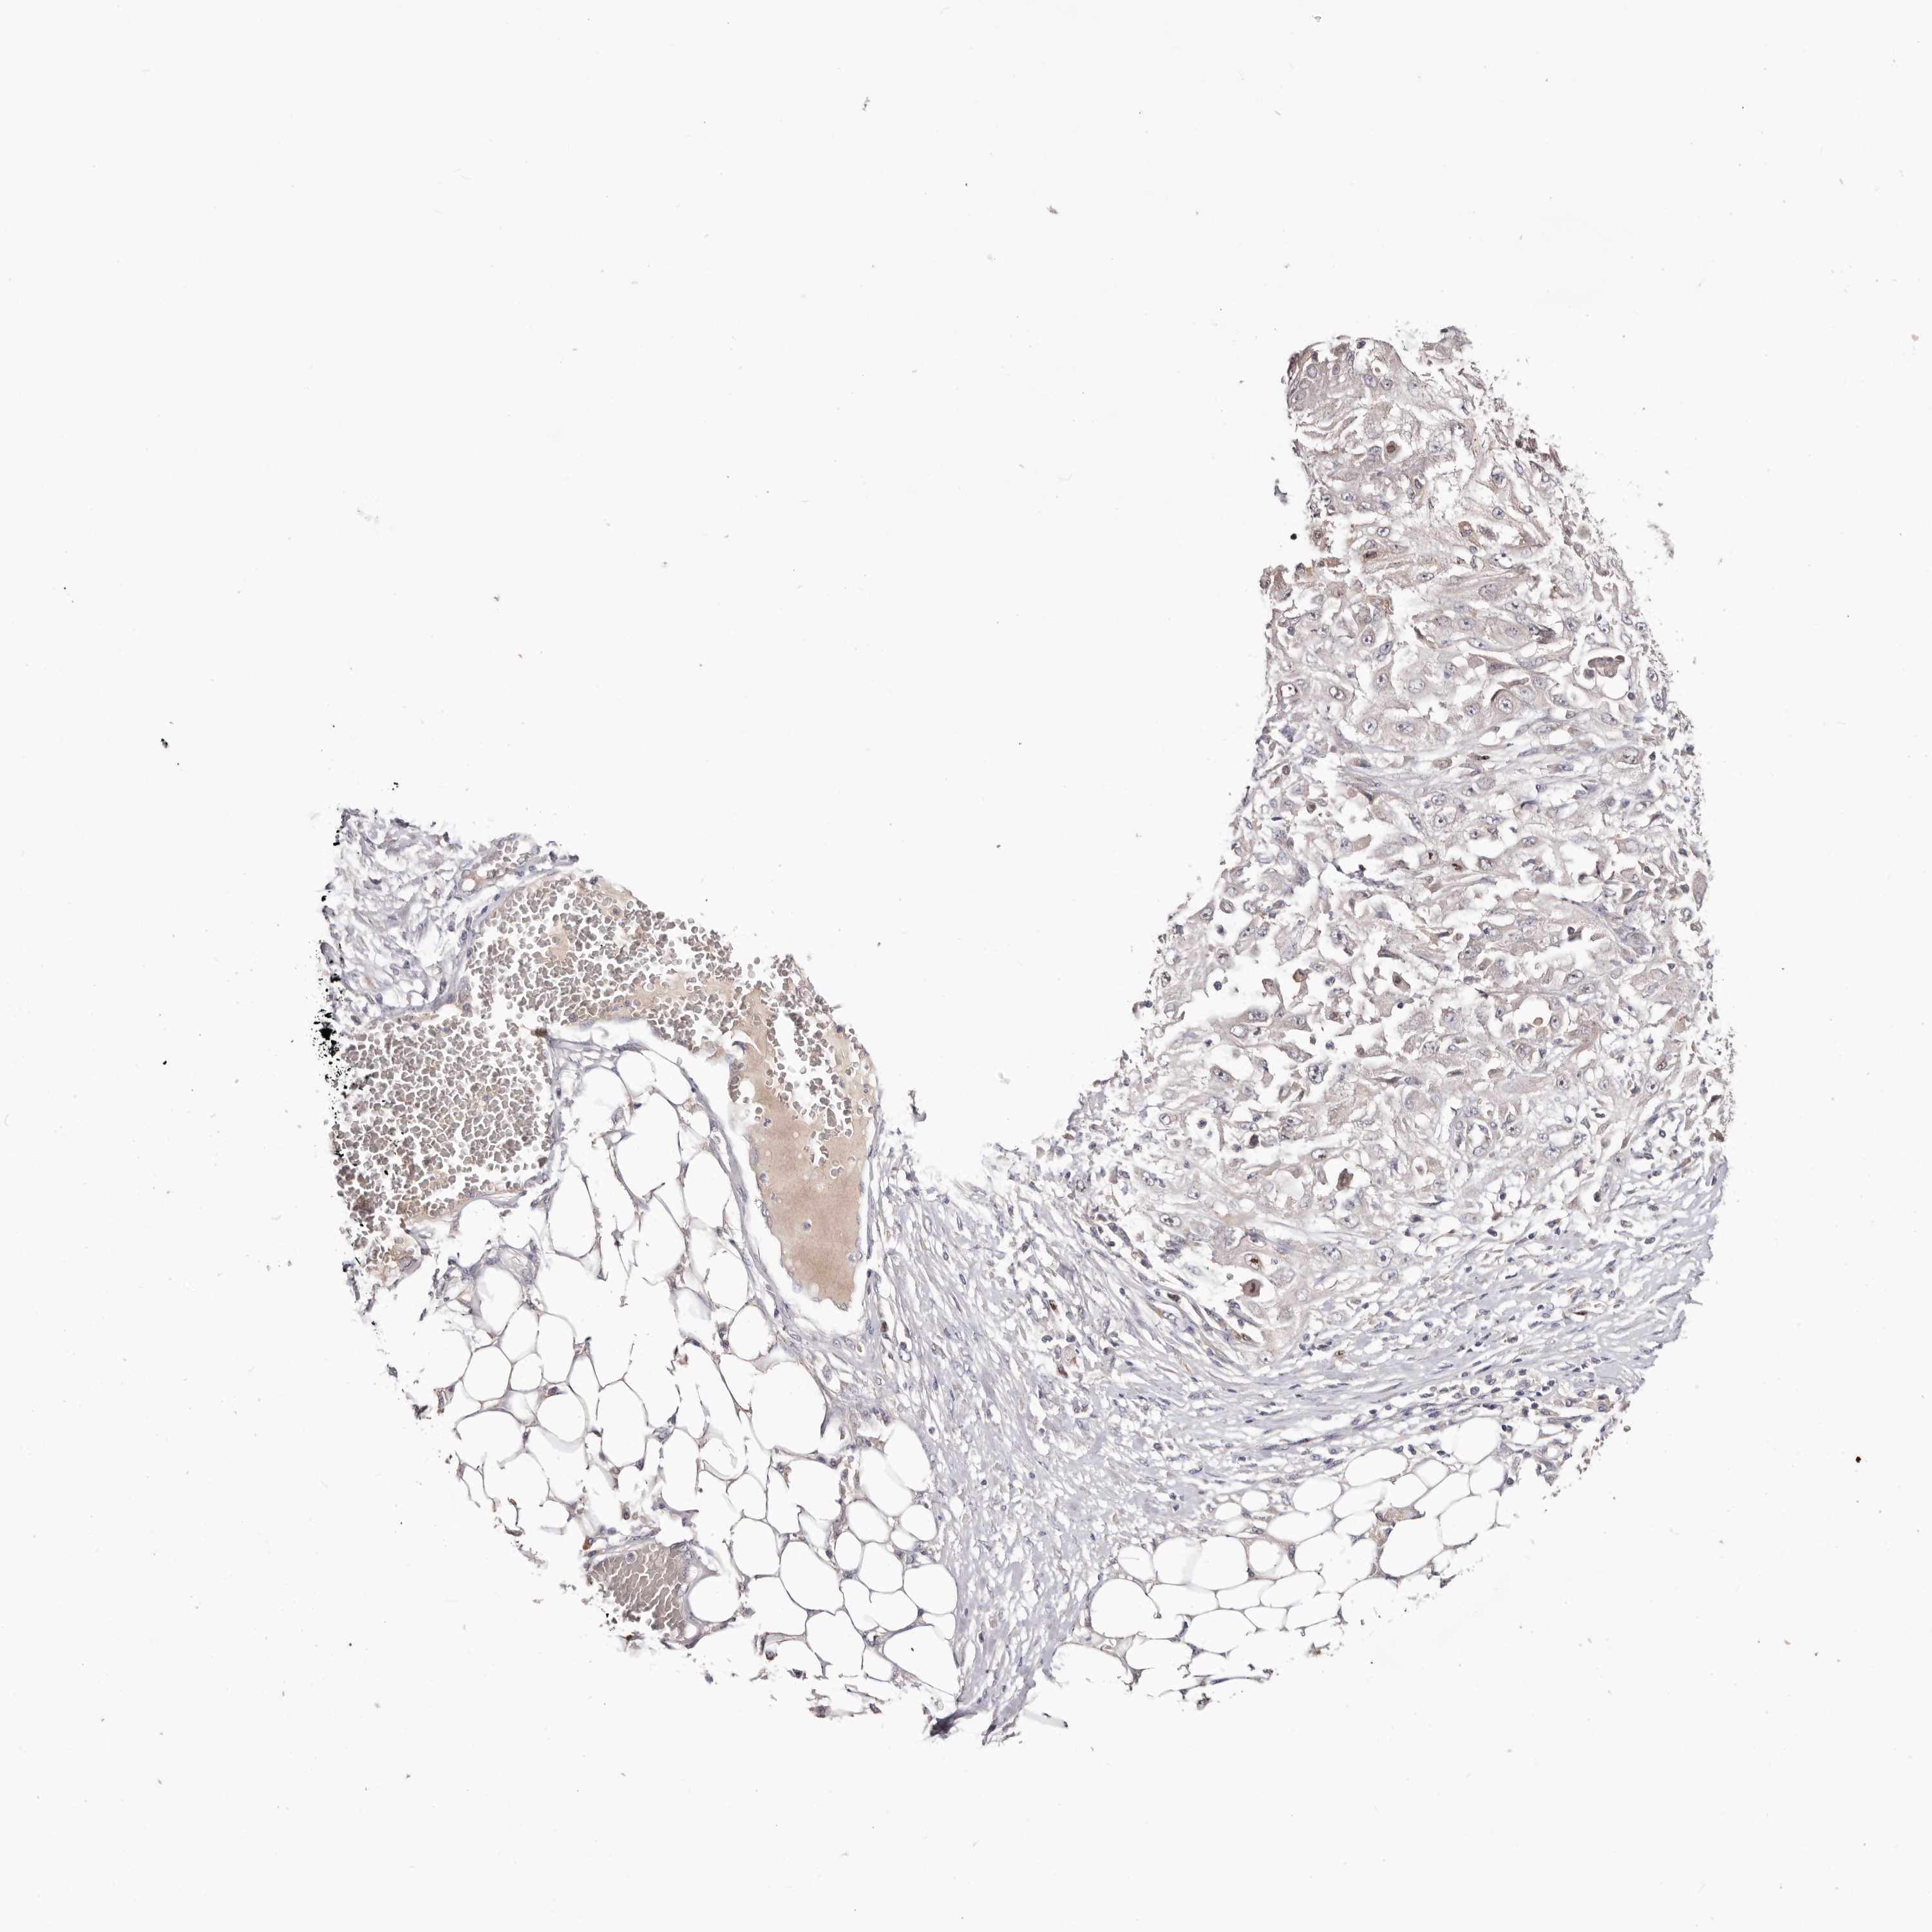

SKIN CANCER - Protein expressioni

A mouse-over function shows sample information and annotation data. Click on an image to view it in a full screen mode. Samples can be filtered based on level of antibody staining by selecting one or several of the following categories: high, medium, low and not detected. The assay and annotation is described here.

Each image is clickable and will lead to virtual microscopy that enables deeper exploration of all samples and also displays staining intensity scores, fraction scores and subcellular localization as well as patient and tissue information for each sample.

Antibody HPA028584

Staining

High

Medium

Low

Not detected

Intensity

Strong

Moderate

Weak

Negative

Quantity

>75%

75%-25%

<25%

None

Location

Nuclear

Cytoplasmic/membranous

Cytoplasmic/membranous,nuclear

Squamous cell carcinoma, NOS

Squamous cell carcinoma, metastatic, NOS